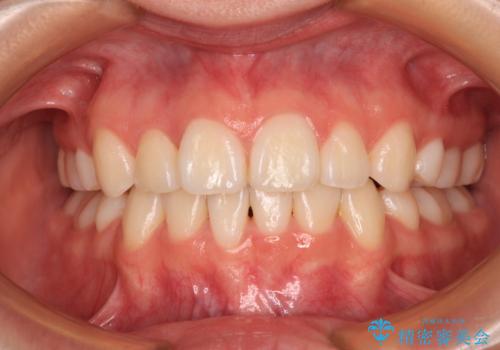

前歯の突出感と上下の隙間 インビザラインによる矯正治療

- 前歯の上下スペースと前歯の隙間を気にして来院された患者様です。

インビザラインにより上下の前歯の隙間を閉じながら、IPRを用いて口元の突出感を合わせて改善していくこととしました。

上下の隙間に舌が入り込むことが、すきっ歯やオープンバイトの原因であったため、舌の筋肉のトレーニングも並行して行い、後戻りの抑制を図りました。